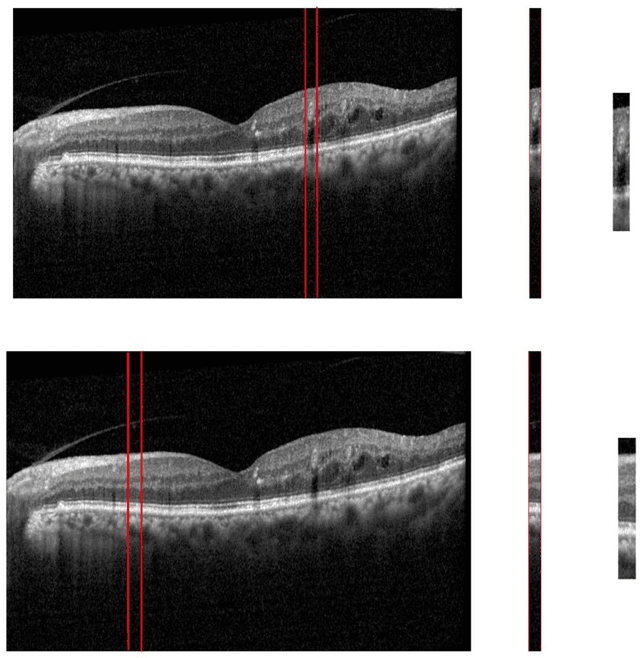

Abstract:Diabetic Retinopathy (DR) caused by diabetes occurs as a result of changes in the retinal vessels and causes visual impairment. Microaneurysms (MAs) are the early clinical signs of DR, whose timely diagnosis can help detecting DR in the early stages of its development. It has been observed that MAs are more common in the inner retinal layers compared to the outer retinal layers in eyes suffering from DR. Optical Coherence Tomography (OCT) is a noninvasive imaging technique that provides a cross-sectional view of the retina and it has been used in recent years to diagnose many eye diseases. As a result, in this paper has attempted to identify areas with MA from normal areas of the retina using OCT images. This work is done using the dataset collected from FA and OCT images of 20 patients with DR. In this regard, firstly Fluorescein Angiography (FA) and OCT images were registered. Then the MA and normal areas were separated and the features of each of these areas were extracted using the Bag of Features (BOF) approach with Speeded-Up Robust Feature (SURF) descriptor. Finally, the classification process was performed using a multilayer perceptron network. For each of the criteria of accuracy, sensitivity, specificity, and precision, the obtained results were 96.33%, 97.33%, 95.4%, and 95.28%, respectively. Utilizing OCT images to detect MAsautomatically is a new idea and the results obtained as preliminary research in this field are promising .